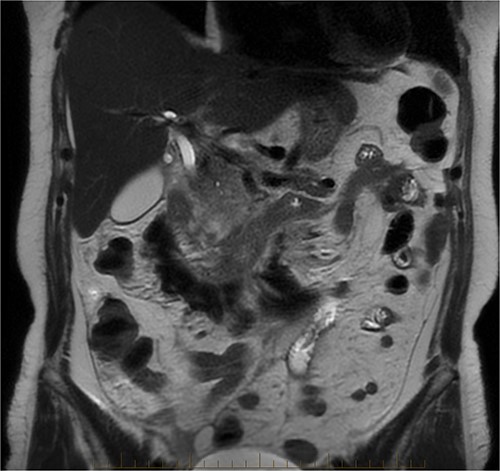

After further discussion with the reporting radiologist, a magnetic resonance imaging (MRI) was performed, which confirmed the presence of an acute periduodenal hematoma surrounding D2 and D3, lying in the retroperitoneal space, anterior to the right perirenal space. Etiology was uncertain. No abnormal enhancement within the bowel to suggest a bowel wall lesion or infiltrating mass (Figs 3 and 4).

MRI abdomen, coronal view. T2 hypointense, T1 iso to hyperintense material surrounding D2/D3 without enhancement in keeping with hemorrhage. No vascular or bowel wall lesion identified.